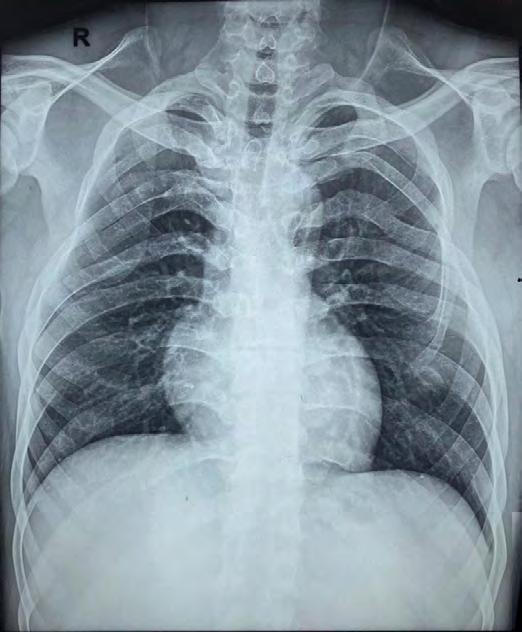

A 28-year-old female presented to the emergency department with right-sided facial swelling, crepitus upon palpation of the right cheek and neck, throat pain and

mild odynophagia, which began three hours after seeing her general dentist for a Class V restoration on tooth #28, a short 15-minute procedure (Figure 1). The patient noticed difficulty swallowing immediately after the procedure, but her dentist attributed the sensation to the effects of anesthesia and sent her home. Her symptoms continued to worsen, at which point she presented to the emergency department for further evaluation.

Laboratory findings upon presentation were significant for a white blood cell count of 16.29 x 109/L. Maxillofacial, neck and chest CTs with contrast were taken, revealing subcutaneous and deep soft-tissue emphysema extending from the right masticator space, through the superficial and deep fascial planes of the neck, into the retropharyngeal space and inferiorly into the mediastinum (Figure 2). The patient was admitted for observation and received intravenous clindamycin. An esophagram was ordered to rule out esophageal perforation.

White blood counts returned to normal one day after admission. Repeat maxillofacial and chest CTs with contrast two days after admission revealed improvement, with decreases in subcutaneous emphysema and tissue edema, and the patient was deemed ready for discharge with continued supportive management at home. The patient was prescribed oral clindamycin and advised to take over-thecounter analgesics as needed. The patient was seen for follow-up in the outpatient oral and maxillofacial surgery clinic two days after discharge; she continued to improve with no signs of worsening infection (Figure 1).

Figure 1. Patient photographs. A: on initial presentation with notable right facial swelling and asymmetry; B: at follow-op 6 days after initial presentation showing improvement.